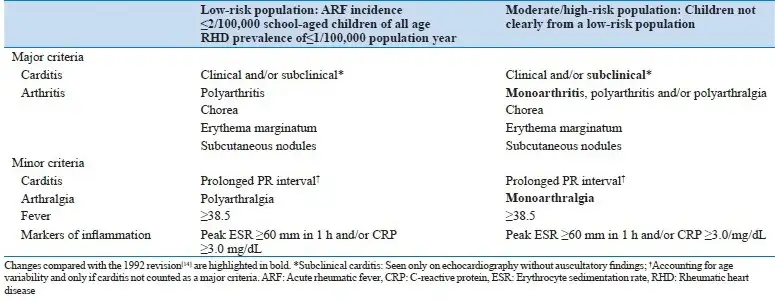

琼斯标准的制定是风湿热诊断史上的里程碑。它不仅为临床医生提供了统一的诊断框架,也为流行病学研究和临床试验奠定了基础。然而,随着对风湿热认识的深入和医学技术的发展,琼斯标准也在不断更新。

2015年,美国心脏协会修订了琼斯标准,纳入了新技术如多普勒超声心动图,以及对疾病流行病学的新认识。修订后的指南考虑了人群内的风险,提供了两条独立的诊断路径,优先考虑低风险人群的特异性和中高风险人群的敏感性。超声心动图现在被推荐用于所有疑似或确诊急性风湿热的患者,亚临床心脏炎可以在所有人群中满足急性风湿热的主要标准。